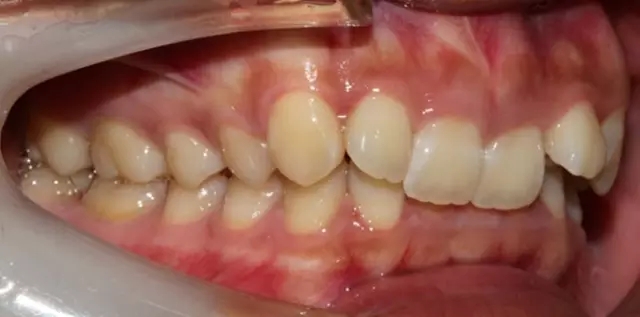

Damon 病例分享:安氏 II 類(lèi)二分類(lèi)露齦笑的矯治(董一磊)

患者信息